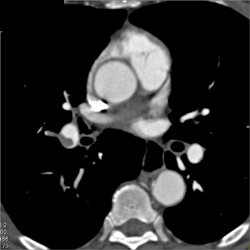

Collapse of Right Upper Lung Bronchus